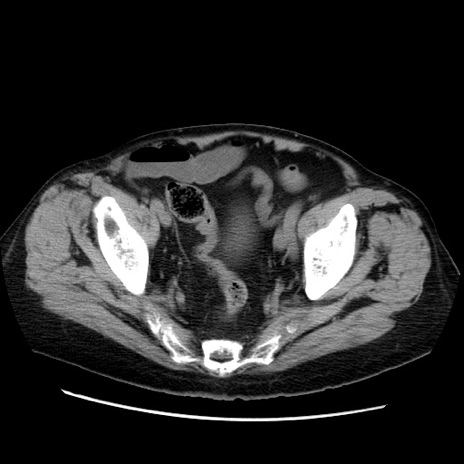

症例21(横断像)

【症例】70歳代男性

【主訴】腹痛

【現病歴】肝硬変・肝細胞癌にてかかりつけの方。約9時間前に食後より腹痛出現。症状が徐々に増悪し、嘔吐出現したため来院。

【既往歴】肝硬変、肝細胞癌(RFA、TACE後)

【身体所見】意識清明、表情苦悶様、BT 36℃、BP 129/78mmHg、P 88bpm、SpO2 97%(RA)、右上腹部から心窩部にかけて圧痛あり、反跳痛なし、筋性防御あり。

【データ】WBC 5800、CRP 0.16